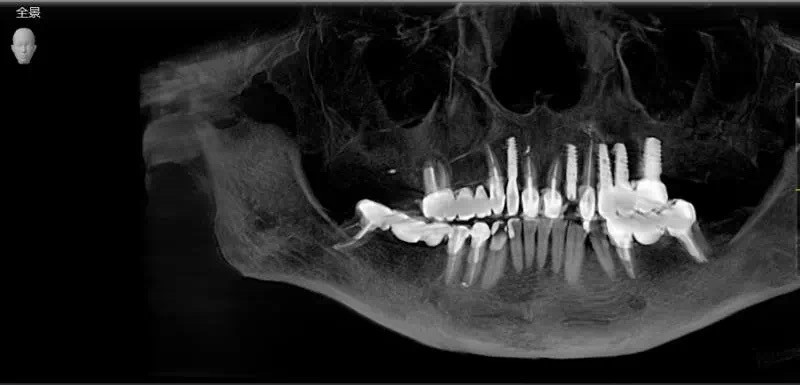

想要进行一次专业安全的种植牙手术,口腔医院必须配备急救设施、所有的医疗器械都必须有专业的消毒中心以及先进的牙齿诊疗设备进行支撑。

种植一颗牙齿,需要术前的基础治疗、种植牙方案的制定、精准的种植手术、术后的定期维护等各方面考量,涉及的学科非常广。

好的种植牙是可以让您沿用一生的,这意味着从种植术前的检查开始就要进行一系列精准地测量与保障。其实,种植牙究竟可以使用多久,取决于三个因素共同决定。

种植牙手术本身就是一个非常复杂且严谨的手术。精准、微创、无痛一个都不能少,海德堡联合口腔UNIC全数字化智能种植体系德国UNIC全数字化智能种植体系到底是什么?将数字化技术与种植理念相结合,保证了种植体精准植入,延长牙齿的使用寿命。